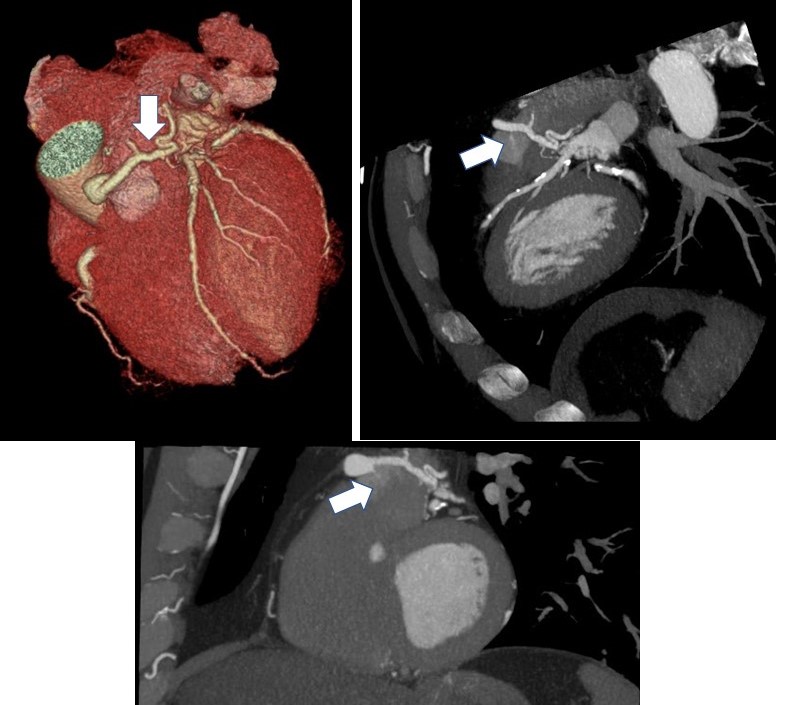

routine #YesCCT incidental finding of a fistulous connection between a branch from the LMCA to the prox PA (white arrow) @Heart_SCCT @LindaGillamMD @mmartinezheart @AtlanticHealth